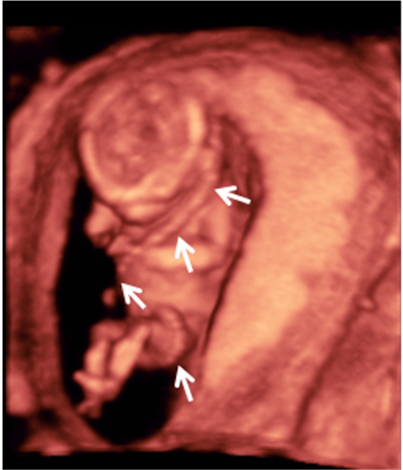

La ecografía Doppler permite comprobar el flujo sanguíneo en el feto y en el cordón umbilical, y así diagnosticar algunas enfermedades o malformaciones cardiacas, entre otras cosas.

Ecografía Embarazo 4D Semana 12 - PRUEBAS DIAGNÓSTICAS